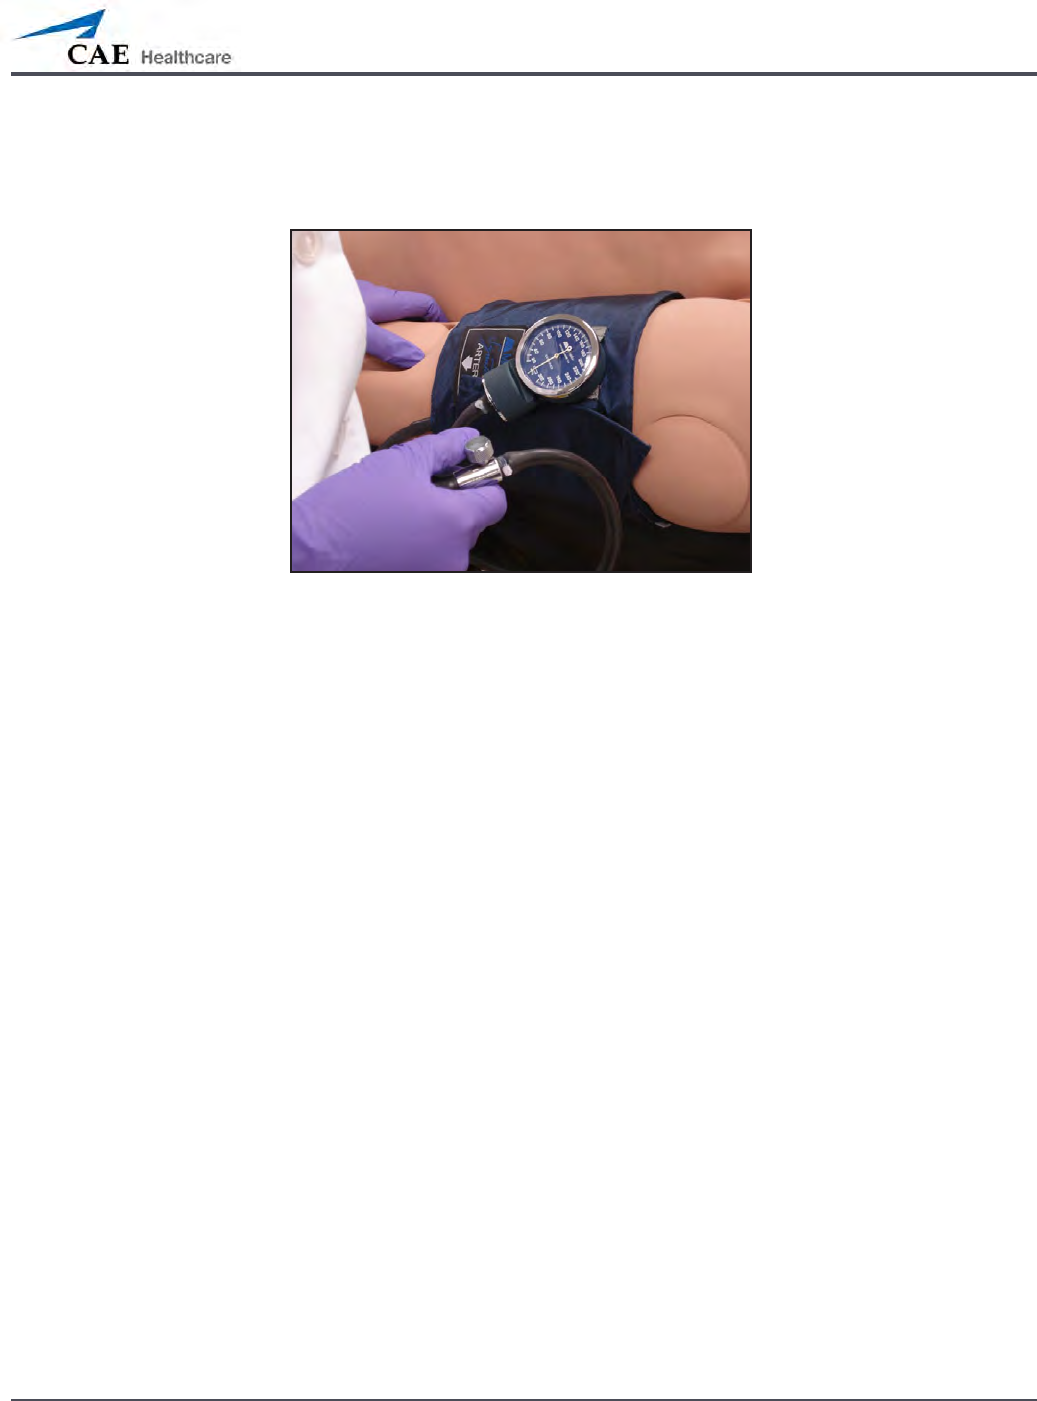

Non-Invasive Blood Pressure Measurement

Blood pressure can be taken manually on either arm. Non-invasive blood pressure (NIBP)

monitoring techniques can be used by attaching the standard cu modied with a T-tting

and adapters.

To get a blood pressure reading, connect the extension from the T-tting on the blood

pressure cu adapter to either of the NIBP ports on METIman’s left and right shoulders.

Connect the T-tting extension to the hose.

Take the non-invasive blood pressure reading using the return-to-ow technique.

Attached Blood Pressure Cu

At appropriate cu pressures, Korotko sounds are produced, and the radial pulse disappears.